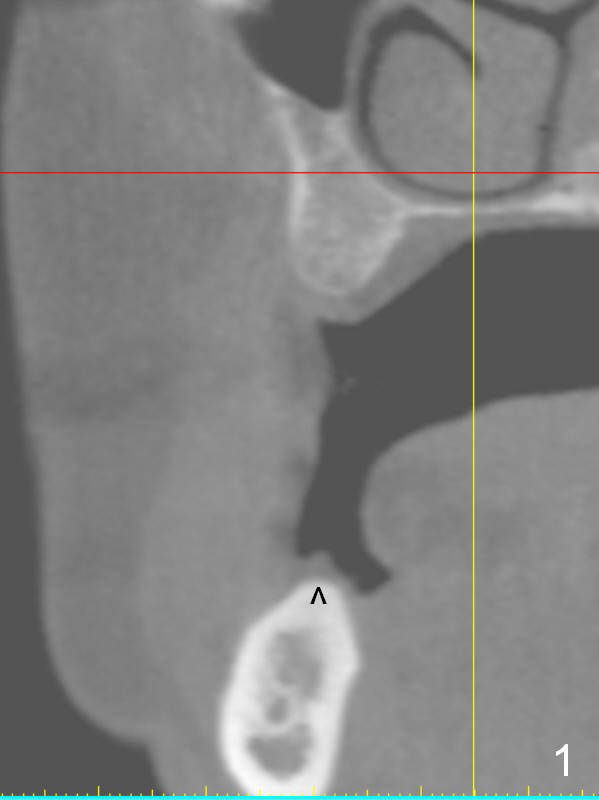

A 49-year-old lady is petit. An implant is placed at #3 and ready for restoration. The crest at #30 is narrow (Fig.1 ^). Bone density at the cortex, around the Inferior Alveolar Canal (IAC) and the medulla is D1, D2 and D3, respectively. It appears that a 10 mm bone-level implant is too close to IAC (Fig.2), whereas a 8 mm one has enough clearance (Fig.3,4). With the same diameter, there will be less thread exposure if the implant is placed a little lingually (Fig.4 (between arrows), as compared to Fig.3).